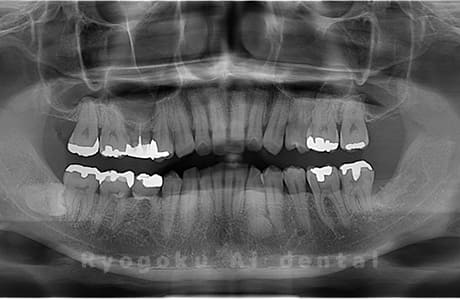

Case01

-

- 原因

- 水平埋伏智歯

- 治療内容

- 下顎の水平埋伏智歯を抜歯

<リスク・副作用>

手術後は痛み、腫れ、痺れなどの副作用が生じる場合があります。